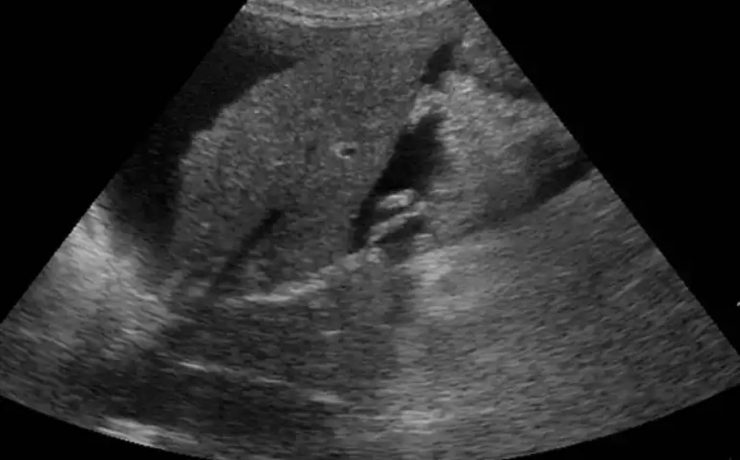

Marcadores ultrasonograficos para enfermedades genéticas

El síndrome de Down es una malformación congénita causada por una alteración del cromosoma 21 (trisomía del par 21) que se acompaña de retraso mental moderado o grave. Debe su nombre a John Langdon Haydon Down quién fue el primero que describió esta condición en 1866, Las personas con